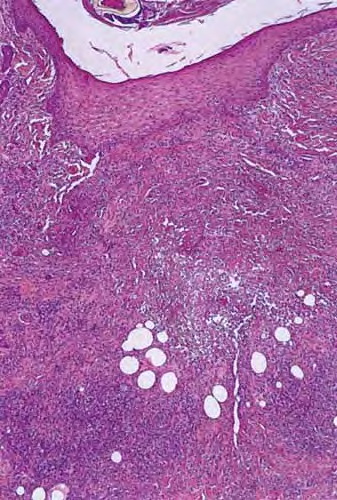

Tick bite =عضة القراد